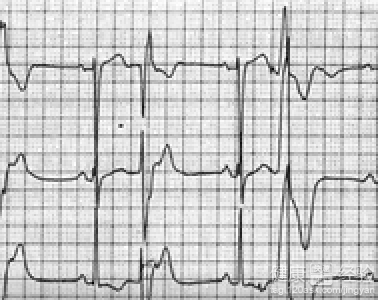

5、反復出現脈搏不齊,冠心病的症狀會出現不明原因心跳過速或過緩者的現象。

10、暈厥,發病時,冠心病的症狀表現為心律紊亂,心率過快,過慢,傳導阻滯,心髒停搏等均可使心排血量減低。由於大腦對缺氧十分敏感,大腦供血不足,輕者感頭昏,重者可出現眩暈甚至暈厥。